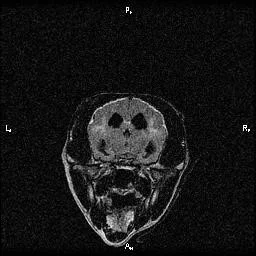

Scout started to show all these signs, and it seemed to be progressing rather rapidly. Well, I'm insatiably curious and I had to know if my buddy was starting to show signs of CCD, or if there was something else going on. Because brain tumors and other diseases can cause these signs too. So Scout had an MRI and a spinal tap at UC Davis.

Typical structural changes in a dog's brain with CCD on MRI include loss of brain tissue, dilation of the fluid-filled ventricles, and shrinkage of the interthalamic adhesion.

He must have read the same text books I was studying at the time, because he even had the structural brain changes that happen with CCD. So, he'd checked all the tick-boxes for me. I went on a search for something that might help.